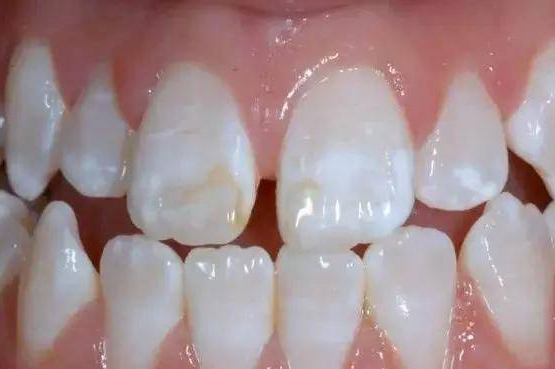

龋齿形成的四个阶段